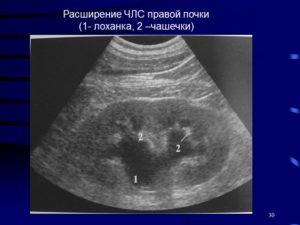

Члс почек

Как правило, когда пациент проходит диагностику УЗИ, в справке с результатом всегда указаны размеры ЧЛС человека. Многие не знают, что такое ЧЛС, и это очевидно. Такая медицинская аббревиатура имеет расшифровку как чашечно-лоханочная система. ЧЛС предназначена для того, чтобы собирать мочевую жидкость.

Первый отдел ЧЛС — это своеобразные чашечки почек, которые весьма точно напоминают бокалы по форме.

Полость лоханки соединена с чашечкой, что создаёт схожесть с воронкой, так как структура сужена в своей нижней части.

Строение стенки ЧЛС из внутреннего слоя слизистого эпителия, средней оболочки из гладкой мускулатуры, и из наружного слоя, выходящего из соединительной ткани.